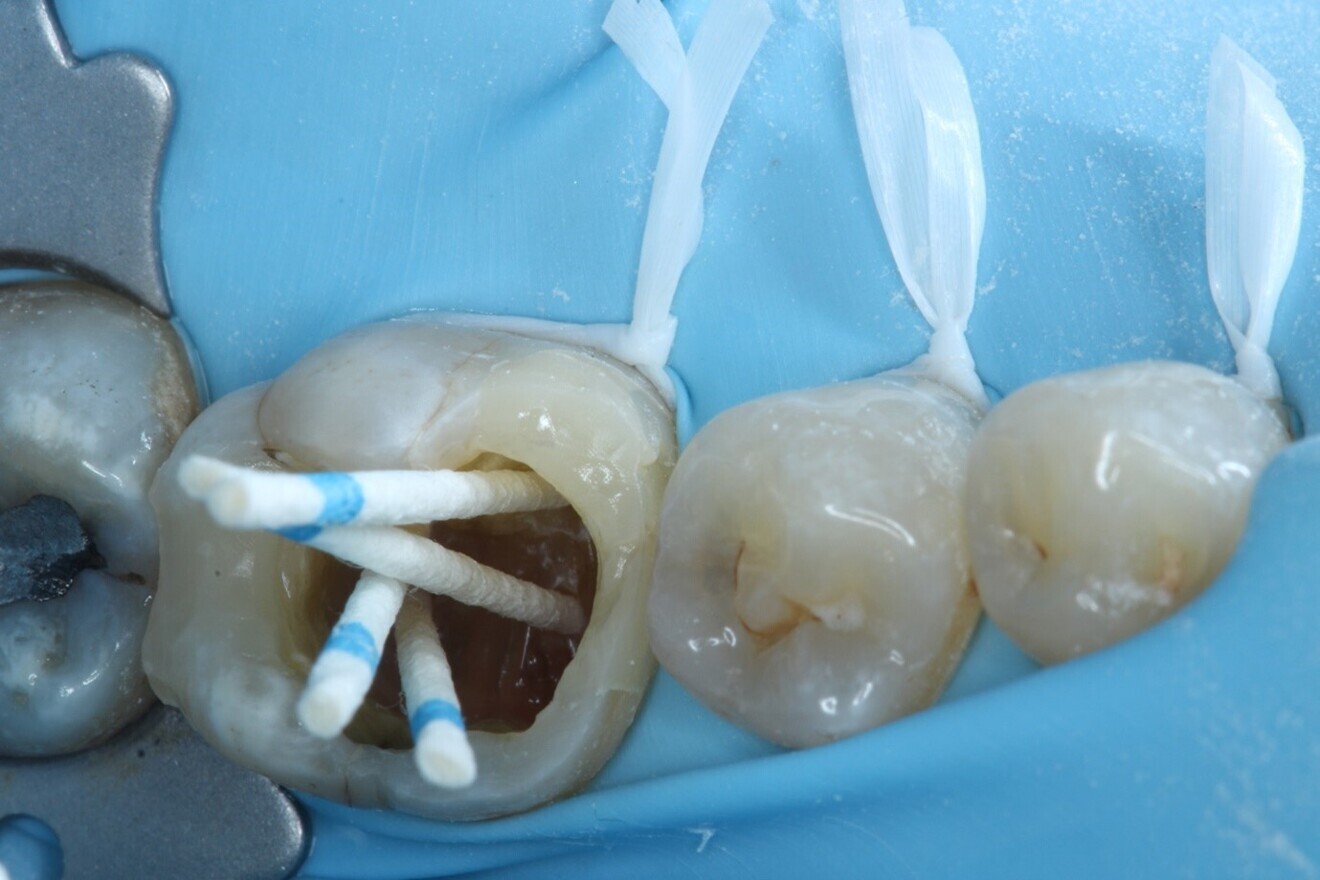

Fig. 3: After caries removal, showing the deep mesial margin.

Local anaesthesia was administered with 4.4 ml of 2% lidocaine hydrochloride with 1:80,000 adrenaline via buccal infiltration and inferior dental nerve block. A dental dam was placed over teeth #37–34 using a HYGENIC Fiesta #7 clamp (COLTENE) and double floss ties to provide a tight seal (Fig. 2). The tooth was reassessed with caries removal having been carried out (Fig. 3), and four orifices located. The mesial cavity margin was deemed restorable; however, deep marginal elevation would be required. A decision was made to carry out the deep marginal elevation after cleaning and shaping of the root canal system to improve or maintain access to the root canal system.

The canals were dried with paper points, a calcium hydroxide paste was placed in the canals and PTFE tape was used in the pulp chamber space. In order to improve the fracture resistance of the tooth in between appointments, deep marginal elevation was carried out with composite for the mesial marginal ridge, utilising a band-in-band technique. The tooth was temporarily restored with a glass ionomer cement, and the occlusion and contacts checked (Figs. 6–8).

Fig. 6: Band-in-band technique using a sectional matrix within a deep marginal elevation band to restore the marginal ridges.